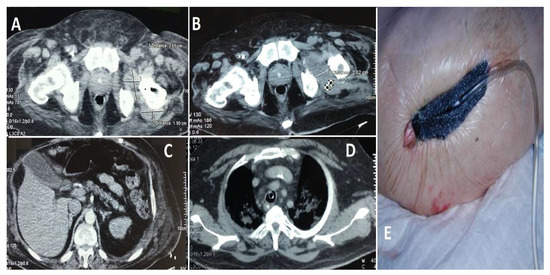

Case 2 (see Figure 7): A 54-year-old male, despite being younger than the typical age for this condition, exhibited a considerable number of comorbidities, including a history of myocardial infarction, diabetes mellitus, persistent smoking, alcohol misuse, and a cachectic appearance. The patient was a pedestrian involved in a road traffic accident three months prior, yet did not seek medical attention at the time. The patient presented at the hospital three months after the incident with severe left hip pain. Imaging and clinical evaluation indicated the presence of purulent discharge from the left hip, while laboratory tests demonstrated a notable elevation in inflammatory markers. The patient was transferred to the ICU with sepsis and underwent a hip osteotomy, followed by the insertion of an antibiotic-impregnated spacer. Following intensive antimicrobial treatment and supportive care in the ICU, the patient’s condition showed signs of improvement. However, due to the presence of chronic health issues and an elevated risk of infection recurrence, the long-term prognosis remained uncertain.

Figure 7. Depicts three images, labeled (AC), which illustrate a significant pelvic abscess that extends along the iliopsoas muscle and reaches the femoral head. This collection indicates a profound infection, with the potential to affect both the muscle and the surrounding joint components. Image (D) illustrates the abscess encircling the femoral head, thereby emphasizing the severity of the infection in this vital anatomical area. Images (E,F) illustrate the conventional anteroposterior and lateral radiographs of the hip joint, respectively. Despite the X-rays failing to provide sufficient information to elucidate the diagnosis, the patient’s ongoing and intense discomfort necessitated additional imaging via a CT scan, which ultimately disclosed the full extent of the illness. Image (G) depicts the surgical debridement of the infected joint focus, accompanied by the insertion of an antibiotic-impregnated cement spacer. The objective of this provisional implant is to manage the infection while ensuring the mechanical stability of the joint. In Image (H), the hip arthroplasty is depicted, conducted approximately six months following the initial surgical procedure, when the infection was successfully managed, thereby allowing for the placement of the definitive prosthesis.